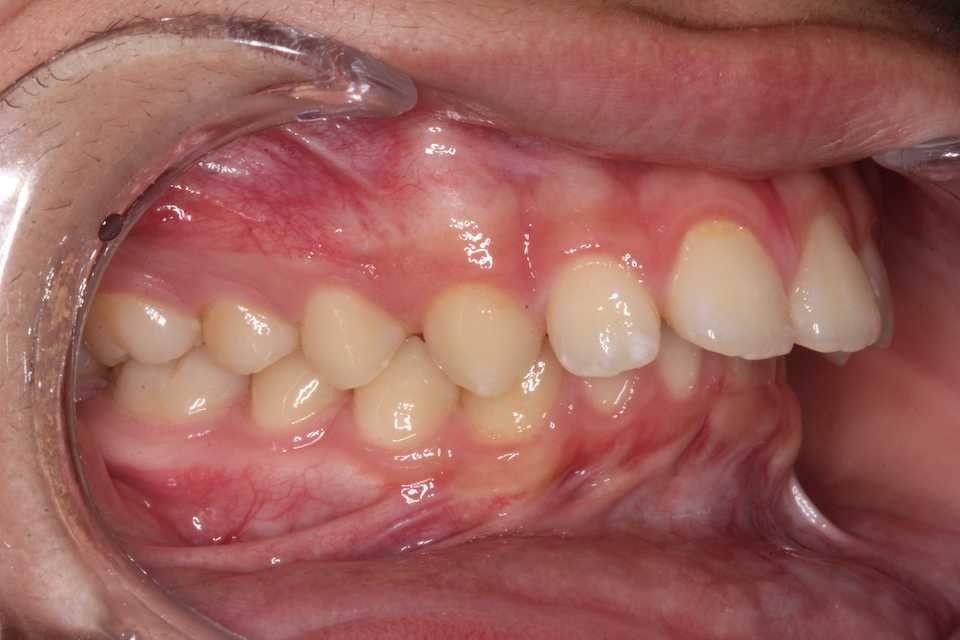

15歳男子、上顎前突観が気になる。出っ歯が気になるのでどうにかならないか?という主訴だったのだが、上下顎の歯列狭窄が見られる。いわゆるディープバイトとはちょっと違うかもしれないが、治療法は基本同じというということでアップしてみたい。ディープバイトは見かけ上の分類に過ぎず、その原因は経験上、強過ぎる咬合力による臼歯部の圧下、咀嚼筋群、口輪筋の過緊張による前歯部の後方傾斜、うつ伏せ寝、横向き寝等の態癖による歯列の狭窄で、それらに伴う下顎後退が特徴的に見られる。この子の場合はうつ伏せ寝により上顎歯列の狭窄(横幅が狭い)し、それに伴い前歯部が外側に弾かれて出っ歯に見える。それだけではなく、噛み締めによる下顎の臼歯部の低位、下唇を噛む等の習癖もあるかもしれない。治療方針は上顎歯列を拡大床装置により拡大しつつ、仰向けで寝るようにして、なるべく前の方で噛んでね。と指示するだけだ。最近は体力の低下でフルブラケット矯正が億劫になってきたので、お金も欲しくないし、なるべく簡単でコストが掛からない方法を考えて実践している。早く綺麗に治そうと思えば最低でも下顎はフルブラケットした方が良いかもしれないが、コストは20倍だ。前回の症例参照。直近の画像は撮るのを忘れたが、だいぶ良くなっている。では時系列でどうぞ寝相等の態癖による典型的な歯列狭窄だ。歯学部では西洋ベル型の歯列と習うが、うつ伏せ寝によってこうなるとは習わない。2ヶ月後